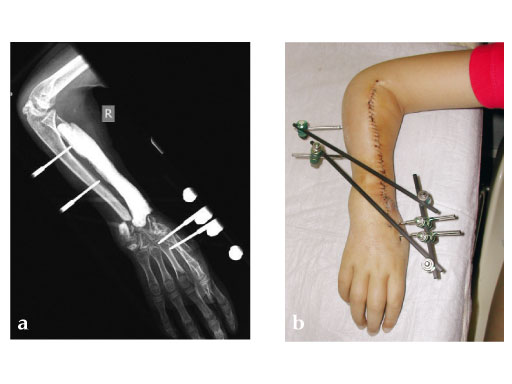

Female, 10 years, after bone tumor (Ewing's sarcoma) resection and allograft implantation, fistula to necrotic allograft.

Fig 2ab: Resection of necrotic radius, temporary ExFix and pallacos spacer.